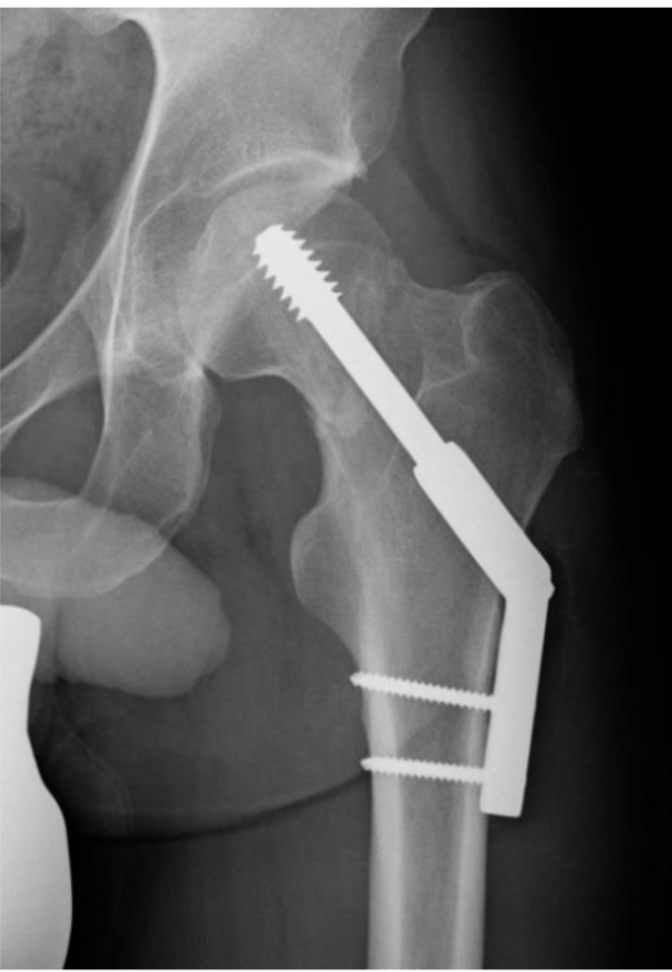

13

Q

What is the general management for extracapsular NOF fractures?

A

Dynamic hip screwe